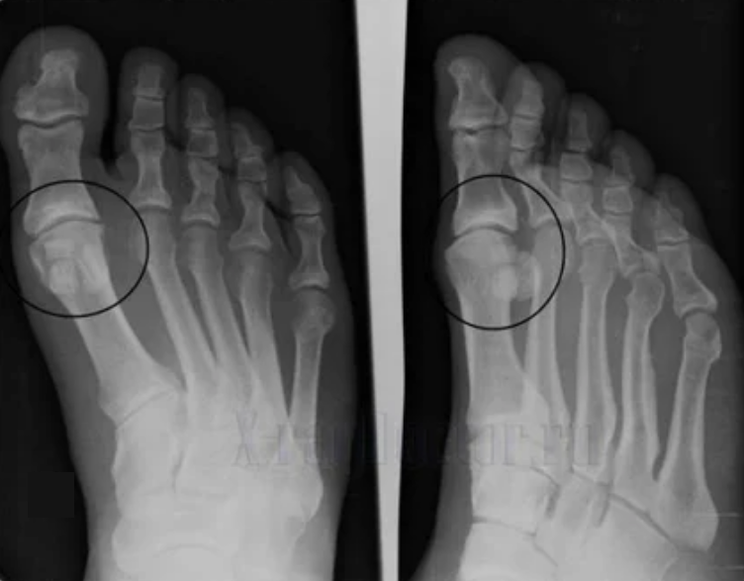

For diagnosis, rheumatologists studied the patient’s complaint and prescribed an X-ray.In most cases, X-rays are used for 2 predictions.Doctors focus on malnutrition in hyacinth cartilage and bone joints.If the joint space is reduced, the bone deformed or flattened, and there is a cystic formation on the surface of the cartilage, bone plants are a clear sign of arthritis.During the examination, arthritis indicates instability of the joints: the limbs and subluxed axes are disturbed.

Typically, X-ray images do not provide complete information about joint conditions.For more thorough research, computed tomography is prescribed to effectively examine bones.MRI is often used to study soft tissues.